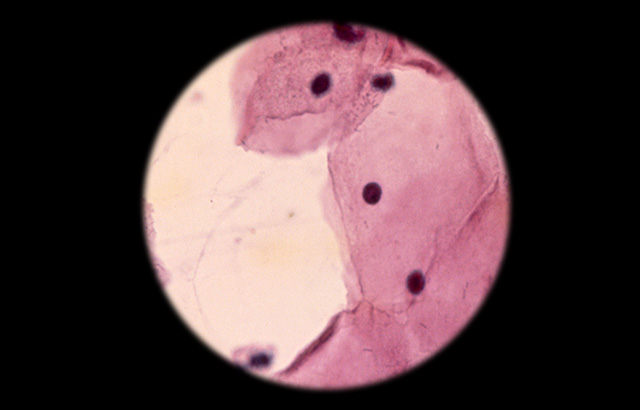

New cervical cancer test has 100 per cent detection rate

A new test for cervical cancer was found to detect all of the cancers in a randomised clinical screening trial of 15,744 women, outperforming both the current Pap smear and human papillomavirus (HPV) test at a reduced cost, according to a study led by Queen Mary University of London.